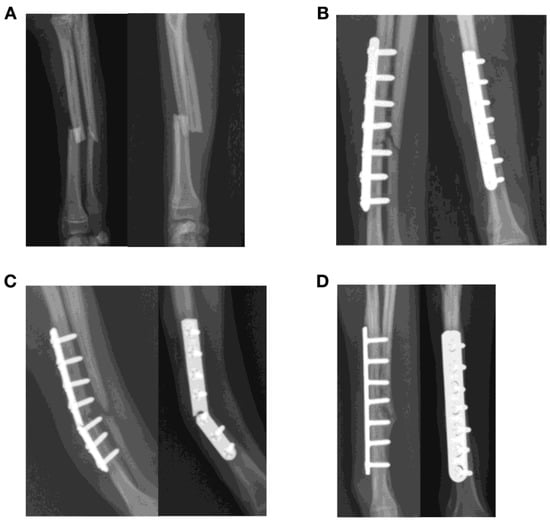

| 1 | Y | Tibia | Diaphyseal | Y | N | 12 | 10 | 12 | 0.83 | 71.9 | 3.5 | 38.5 | 3.5 mm DCP | 32.94 | Medial |

| 2 | Y | Tibia | Diaphyseal | Y | Y | 13 | 7 | 8 | 0.62 | 95.8 | 2.6 | 41.4 | 1.5/2.0 LCP | 0.79 | Medial |

| 3 | N | Tibia | Diaphyseal | Y | N | 11 | 9 | 10 | 0.91 | 77.1 | 2.8 | 26.0 | 3.5 mm broad DCP | 46.7 | Medial |

| 11 | Y | Tibia | Diaphyseal | Y | N | 14 | 10 | 9 | 0.79 | 62.1 | 3.2 | 6.3 | Stacked 1.5 mm cuttable plate with spaces (VI) | 2.8 | Medial |